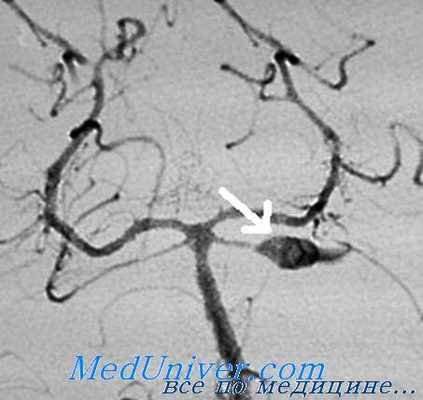

Внутрисосудистым методом были оперированы 92 пациента, которым было выполнено 96 внутрисосудистых операций. Хороший исход лечения (OGS 5–4) к моменту выписки имели 79,3% больных. Удовлетворительный (OGS 3) результат лечения был достигнут у 11% больных. Неудовлетворительный результат (OGS1–2) отмечен у 9,7% больных с летальностью 5,4% (рис. 4).

Рис. 4. Функциональный исход внутрисосудистых операций

Нами была выявлена определённая зависимость между функциональным исходом лечения и типом строения мешка аневризм. Неудовлетворительный функциональный исход встречался достоверно чаще после операций на аневризмах с фузиформноподобным типом строения - частота неблагоприятных исходов (OGS I-II) (21%) была выше, чем при операциях на мешотчатых и фузиформных аневризмах (p<0,01). Частота благоприятных исходов (OGS IV-V) была выше у больных с мешотчатыми и фузиформными аневризмами (86,3% и 100% соответственно), чем у больных с фузиформноподобными аневризмами (63,5%). Различие статистически достоверно (p<0,05).